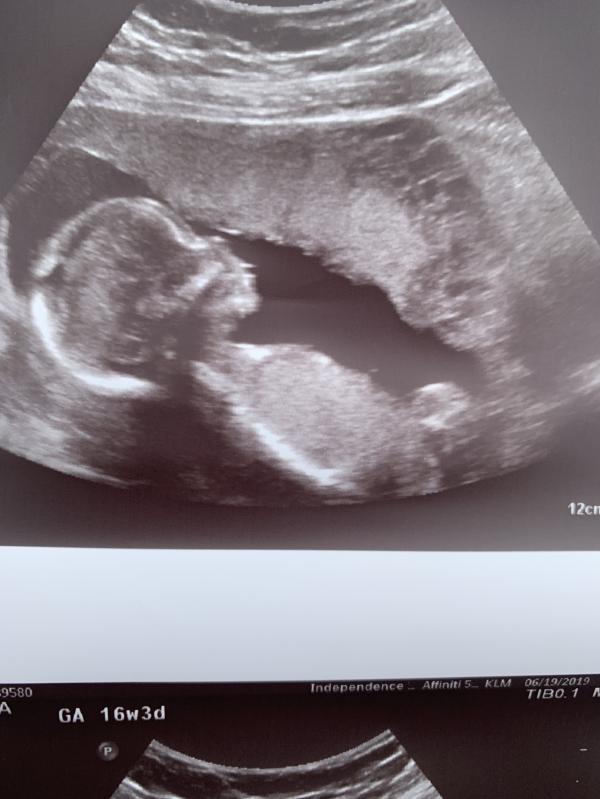

My little cousin do you guys think it’s a boy or a girl?